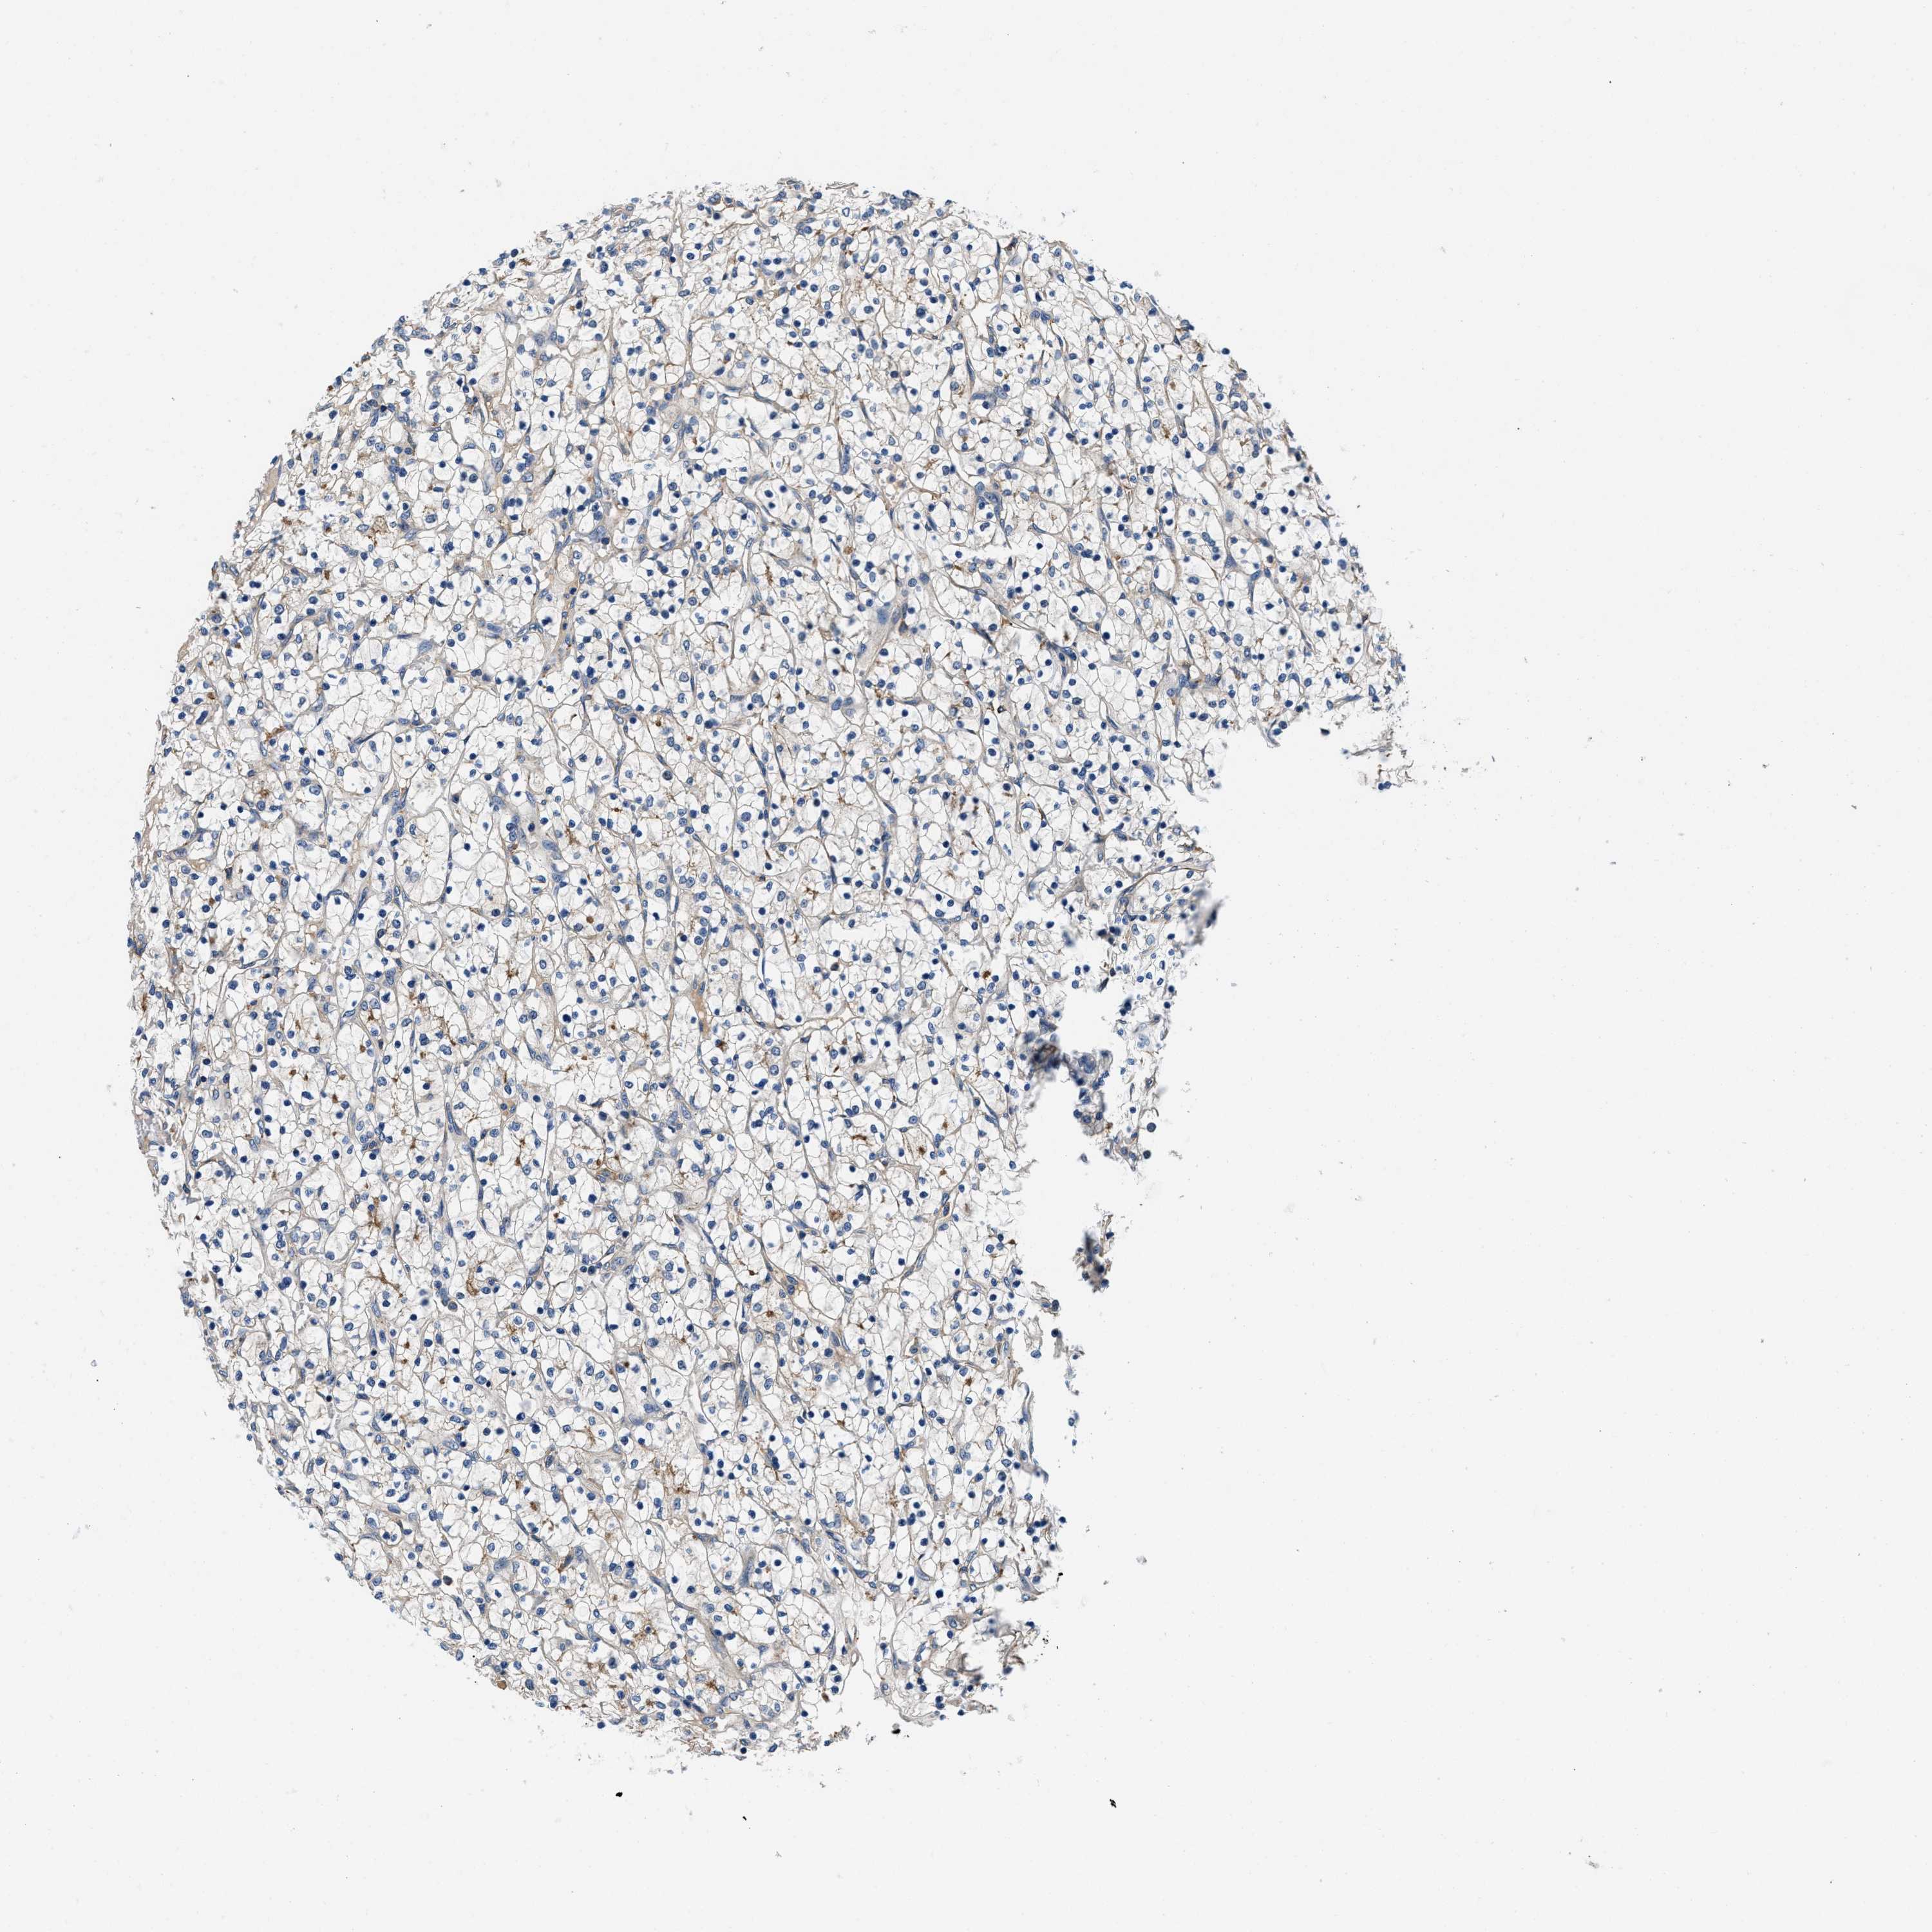

KIDNEY RENAL CLEAR CELL CARCINOMA (VALIDATION) - Interactive survival scatter ploti

The Survival Scatter plot shows the clinical status (i.e. dead or alive) for all individuals in the patient cohort, based on the same data that underlies the corresponding Kaplan-Meier plots. Patients that are alive at last time for follow-up are shown in blue and patients who have died during the study are shown in red.

The x-axis shows the expression levels (FPKM) of the investigated gene in the tumor tissue at the time of diagnosis. The y-axis shows the follow-up time after diagnosis (years). Both axes are complimented with kernel density curves demonstrating the data density over the axes. The top density plot shows the expression levels (FPKM) distribution among dead (red) and alive patients (blue). The right density plot shows the data density of the survived years of dead patients with high and low expression levels respectively, stratified using the cutoff indicated by the vertical dashed line through the Survival Scatter plot. This cutoff is automatically defined based on the FPKM cutoff that minimizes the p-score. The cutoff can be changed by dragging the vertical line or by entering a cutoff value in the square labeled "Current cut-off".

Under the Survival Scatter plot the p-score landscape (black curve; left axis) is shown together with dead median separation (red curve; right axis). Dead median separation is the difference in median mRNA expression between patients who have died with high and low expression, respectively. It is calculated as follows: median FPKM expression of dead patients with high expression - median FPKM expression of dead patients with low expression. This is intended to aid the user in visually exploring custom cutoffs and the associated p-scores and dead median separation.

Individual patient data is displayed and can be filtered by clicking on one or more of the category buttons on the top of the page. Categories describing expression level and patient information include: high, low, alive, dead, female, male and tumor stages. The scale of the x-axis can be toggled between linear and log-scale by clicking on the "x log" button. Mouse-over function shows TCGA ID, patient information and mRNA expression (FPKM) for each patient.

& Survival analysisi

Kaplan-Meier plots summarize results from analysis of correlation between mRNA expression level and patient survival. Patients were divided based on level of expression into one of the two groups "low" (under cut off) or "high" (over cut off). X-axis shows time for survival (years) and y-axis shows the probability of survival, where 1.0 corresponds to 100 percent.

ZFAND3 is not prognostic in Kidney Renal Clear Cell Carcinoma (validation)

Best expression cut offi

Based on the FPKM value of each gene, patients were classified into two groups and association between prognosis (survival) and gene expression (FPKM) was examined. The best expression cut-off refers the FPKM value that yields maximal difference with regard to survival between the two groups at the lowest log-rank P-value. Best expression cut-off was selected based on survival analysis .

When clicking on this number, the vertical dashed line indicating cut-off, the interactive survival plot, and the Kaplan-Meier curve will be adjusted to show results based on the best expression cut-off.

: 52.03

TCGA RNA samplesi

RNA-seq data is reported as average FPKM (number Fragments Per Kilobase of exon per Million reads), generated by the The Cancer Genome Atlas (TCGA) .

Normal distribution across the dataset is visualized with box plots, shown as median and 25th and 75th percentiles. Points are displayed as outliers if they are above or below 1.5 times the interquartile range. FPKM values of the individual samples are presented next to the box plot.

Average pTPM 62.4

Number of samples 100